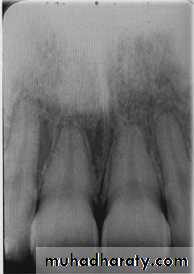

Examination of bone:Height of alveolar bone

Crest relative to teeth

Loss of height-more than 1.5 mm periodontal disease

Lamina dura + PDL space + tooth roots